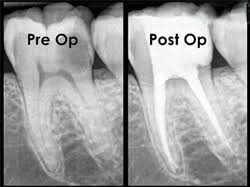

Before and After Images

Our Root Canal Treatment Experiences

Root Canal Therapy

X-rays are taken to determine the extent of the damage. Local anesthesia is administered to numb the area.An opening is made in the crown of the tooth to access the pulp.The infected or damaged pulp is removed, and the root canals are cleaned and shaped The cleaned canals are filled with a biocompatible material, usually gutta-percha.